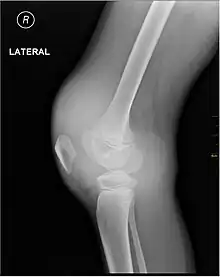

Synovial fluid analysis is another method to diagnose Hemarthrosis. It involves a small needle being inserted into the joint to draw the fluid.[6] Reddish-colored hue of the sample is an indication of the blood being present. Imaging tests are normally done. The tests also include MRI, ultrasound and X-ray test, which give better information about the joint inflammation.[7] Although MRI is superior method for this assessment, the US using the HEAD-US method performed by paediatric radiologists is a reliable tool for detection and quantification of haemophilic arthropathy in children in comparison to MRI.[8]